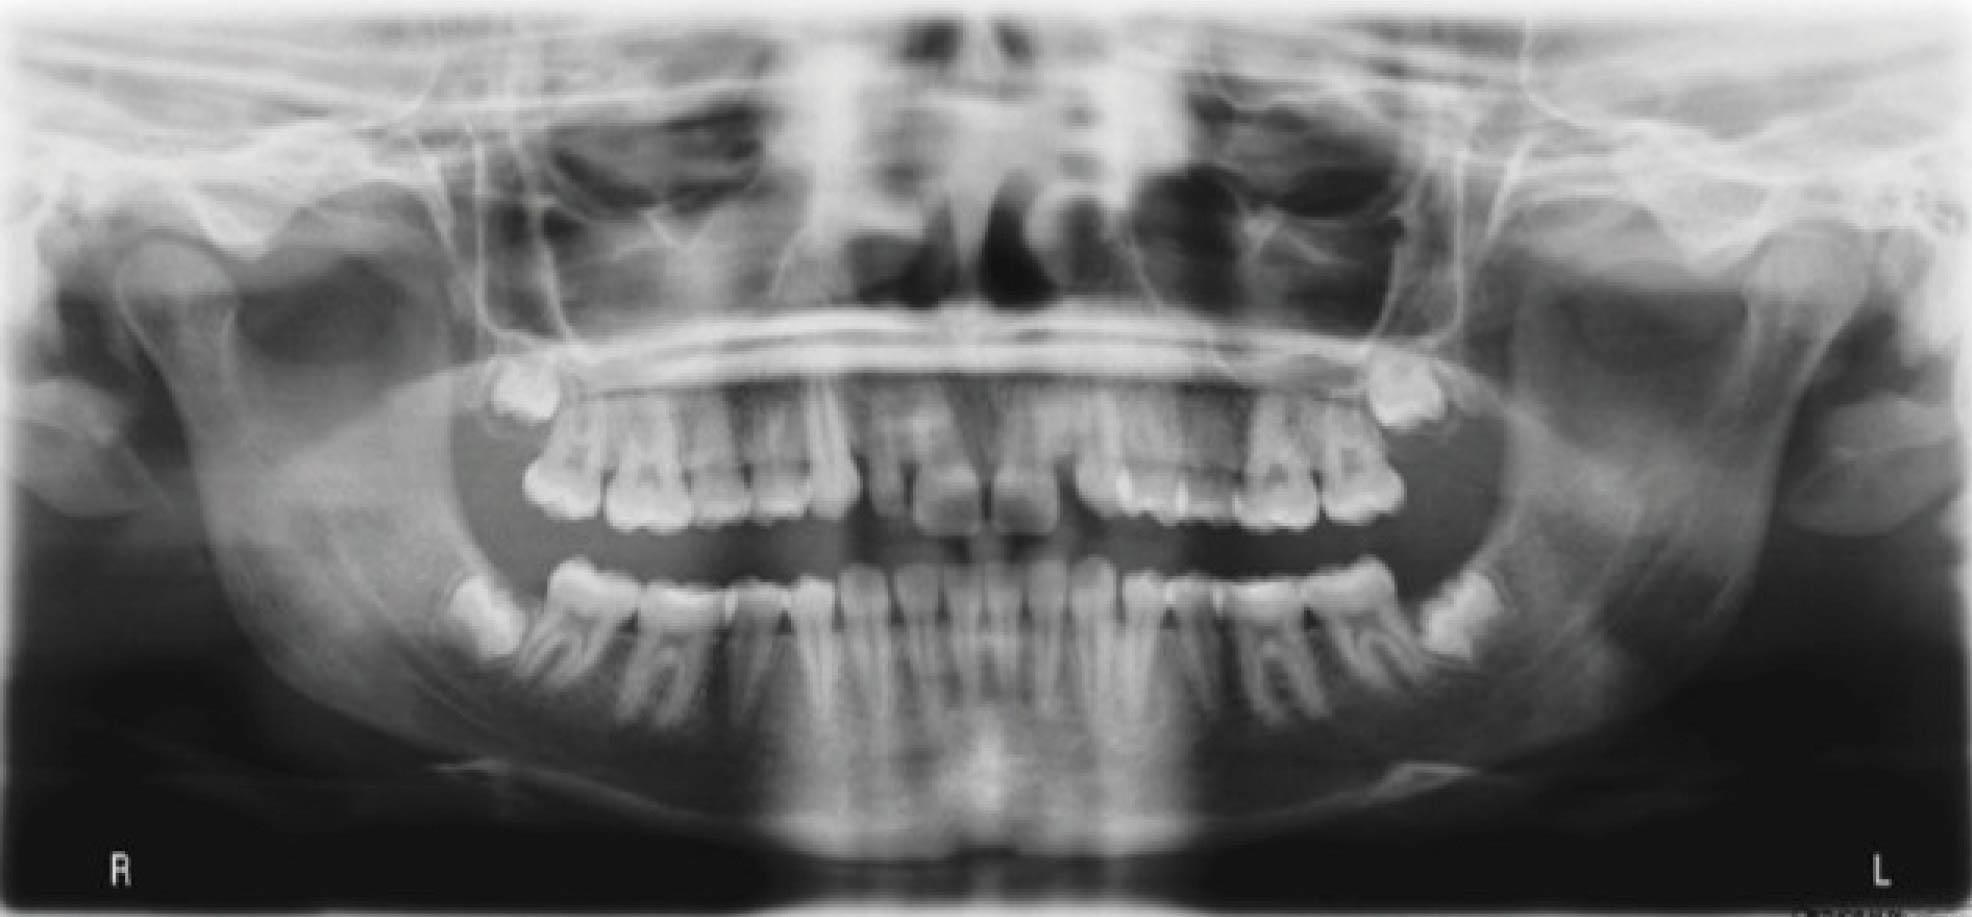

اگر برش الاینر در چند هفته پایانی درمان باعث بسته شدن بایت نشد، باید چند باتن روی دندانهای خلفی بچسبانید و الاستیک عمودی بدهید تا اکلوژن خلفی مجدد برقرار گردد (شکلهای 176-6 و 177-6).

مجدد تاکید میکنم که شانس بروز اپن بایت خلفی در طرح درمانهای کامپیوتری که متناسب با اصول این کتاب باشند خیلی کم است. معمولاً باتن و الاستیک به ندرت نیاز میشود. کنترل تماسهای پیشرس قدامی از همان ابتدای درمان، کلید مهمی در جلوگیری از اپن بایت خلفی است

شکل 176-6

شکل 177-6